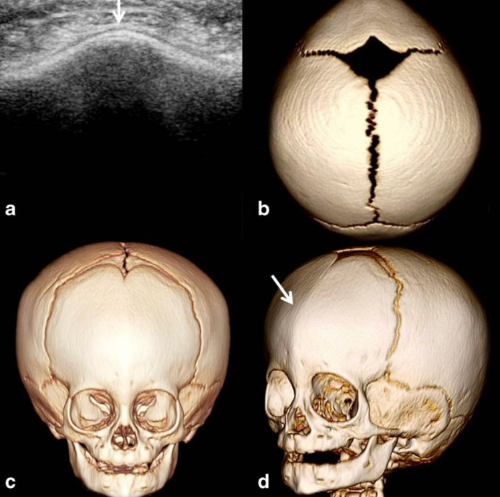

아래는 전두봉합 조기유합 환아의 두개골 3D 영상입니다.

b, c, d 이미지를 보면 정상적으로는 이마 쪽까지 이어져 있어야 할 전두봉합이 이미 닫혀 있는

모습을 확인할 수 있습니다.

이와 함께 앞서 설명한 것처럼 위에서 보았을 때

이마가 삼각형으로 뾰족한 형태를 뚜렷하게 보이고 있습니다.